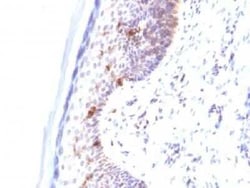

CD1a Antibody (C1A/711) - IHC-Prediluted, Novus Biologicals™

CD1a Monoclonal antibody specifically detects CD1a in Human samples. It is validated for Immunohistochemistry, Immunohistochemistry (Paraffin)

| Immunohistochemistry, Immunohistochemistry (Paraffin) | |

| Immunohistochemistry, Immunohistochemistry-Paraffin 0.5 - 1.0 μg/mL | |

| Recombinant full-length human CD1a protein (Uniprot: P06126) | |